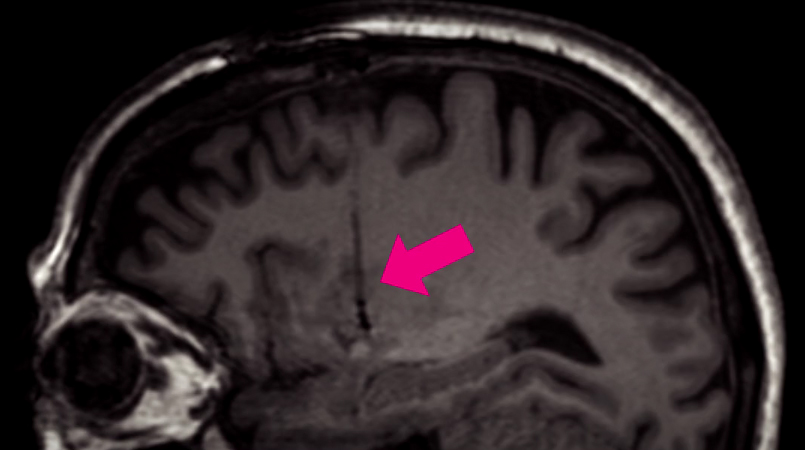

The report expands on previous data from Voyager Therapeutics phase Ib clinical trial, in which 15 participants with advanced Parkinson’s have been treated with one of three doses of VY-AADC01. The participants were all treated with a single administration of VY-AADC01 (this is a surgical procedure which involves a syringe being inserted into the brain, and guided down into the putamen where the virus is injected).

Targeting the putamen (pink arrow indicates the syringe tract). Source: LCT

The primary endpoint (the main measure of assessment) of this Phase I study is the safety and tolerability of VY-AADC (as well as testing ascending doses of the virus), which is measured by the number of adverse events. The secondary endpoint of the study was a brain imaging approach (18F-DOPA) which allows for measures of the conversion of L-dopa into dopamine. Unfortunately, the update provides no information regarding the secondary endpoints.